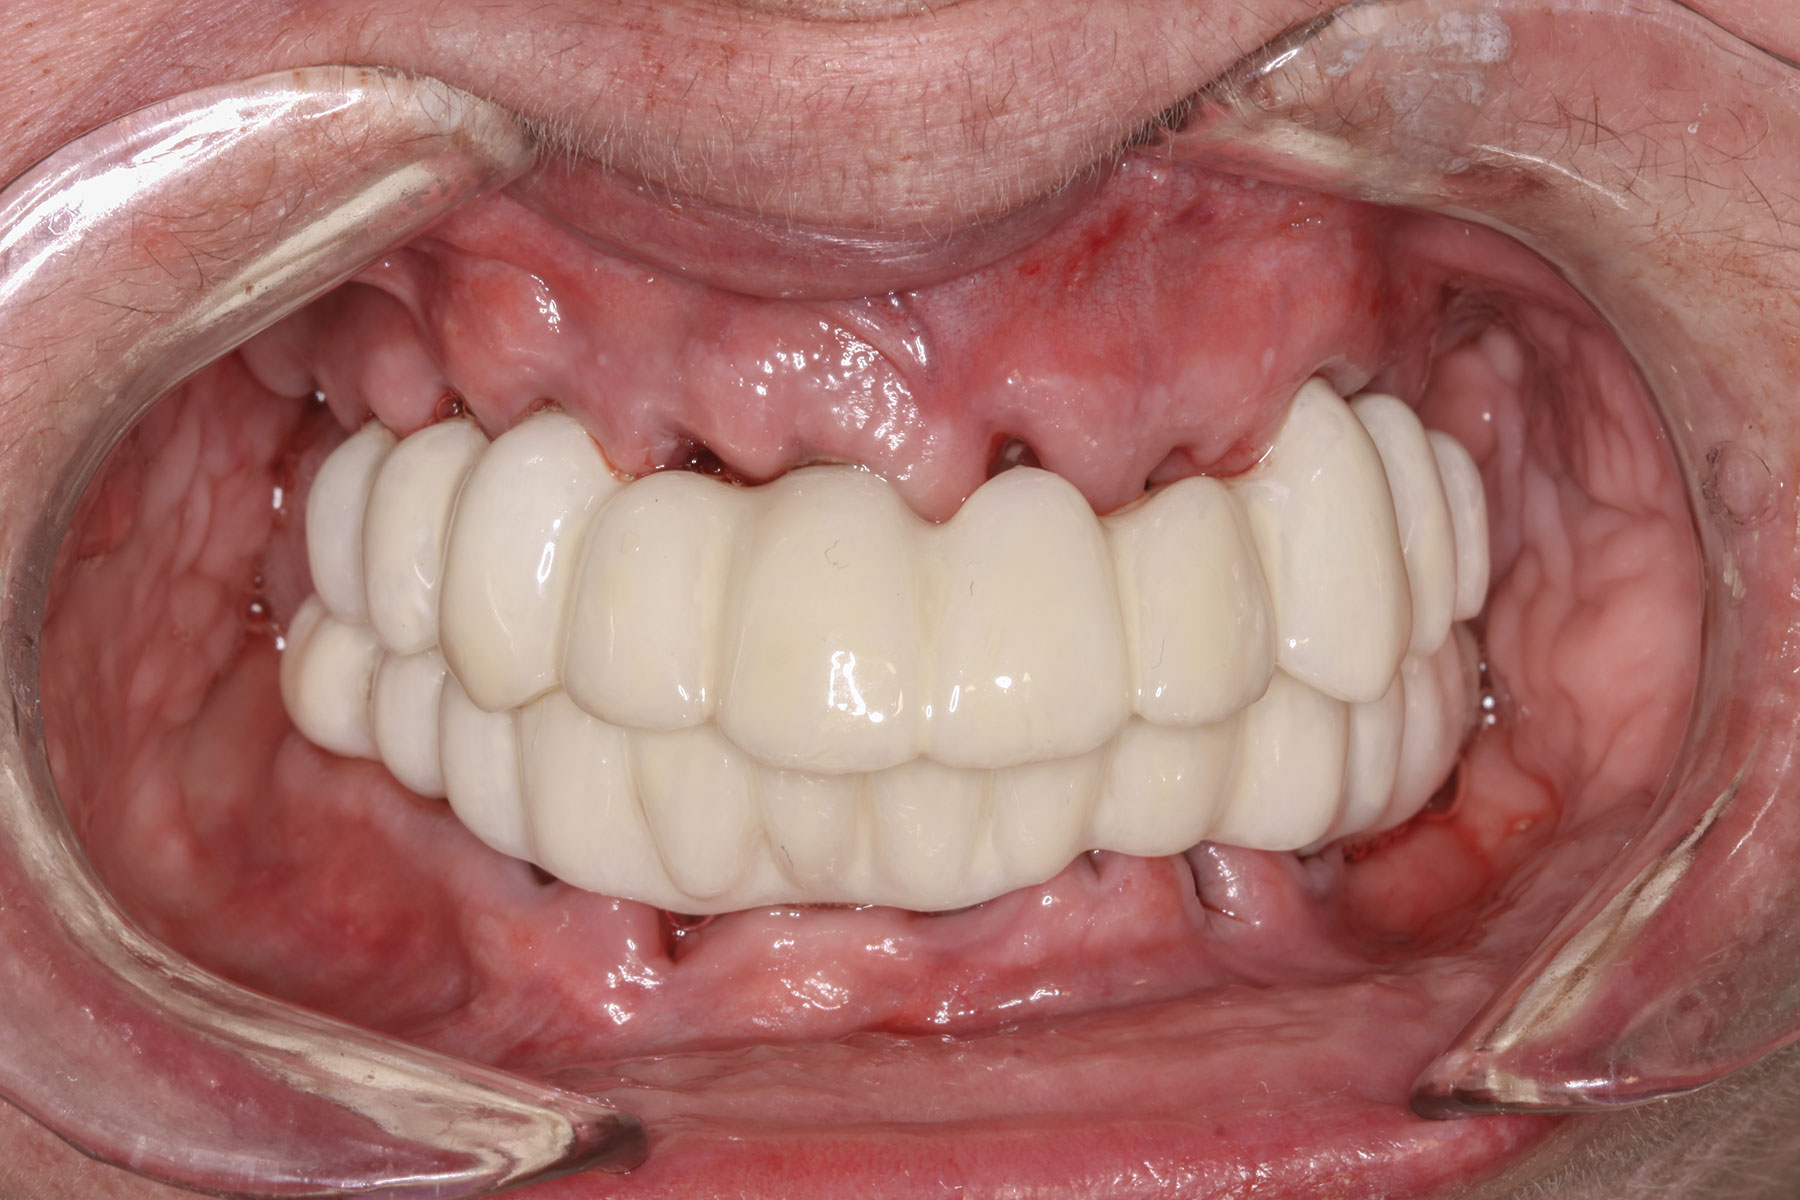

Fig 18. Implants and provisional maxillary prosthesis in place, the same day as surgery.

Figure 18

The prosthesis fit precisely on the multi-unit abutments, and multi-unit screws were used to secure the prosthesis in place at 20 Ncm (Figure 18 through Figure 20). The screw-access holes were filled, and the patient was instructed on dietary restrictions and adherence to a soft diet. Instructions for oral hygiene were given, and the patient was advised to use a water flosser daily. Analgesics included ibuprofen 800 mg, and for antibiotics, amoxicillin 500 mg three times a day was prescribed.

Postoperative x-rays documented the full seating of the prosthesis on the multi-unit abutments (Figure 21 and Figure 22). The patient returned at 1 week postoperatively for a follow-up visit and to review home care. She remarked that the restoration was comfortable and that she was free of discomfort and extremely pleased with the makeover she received in one day.